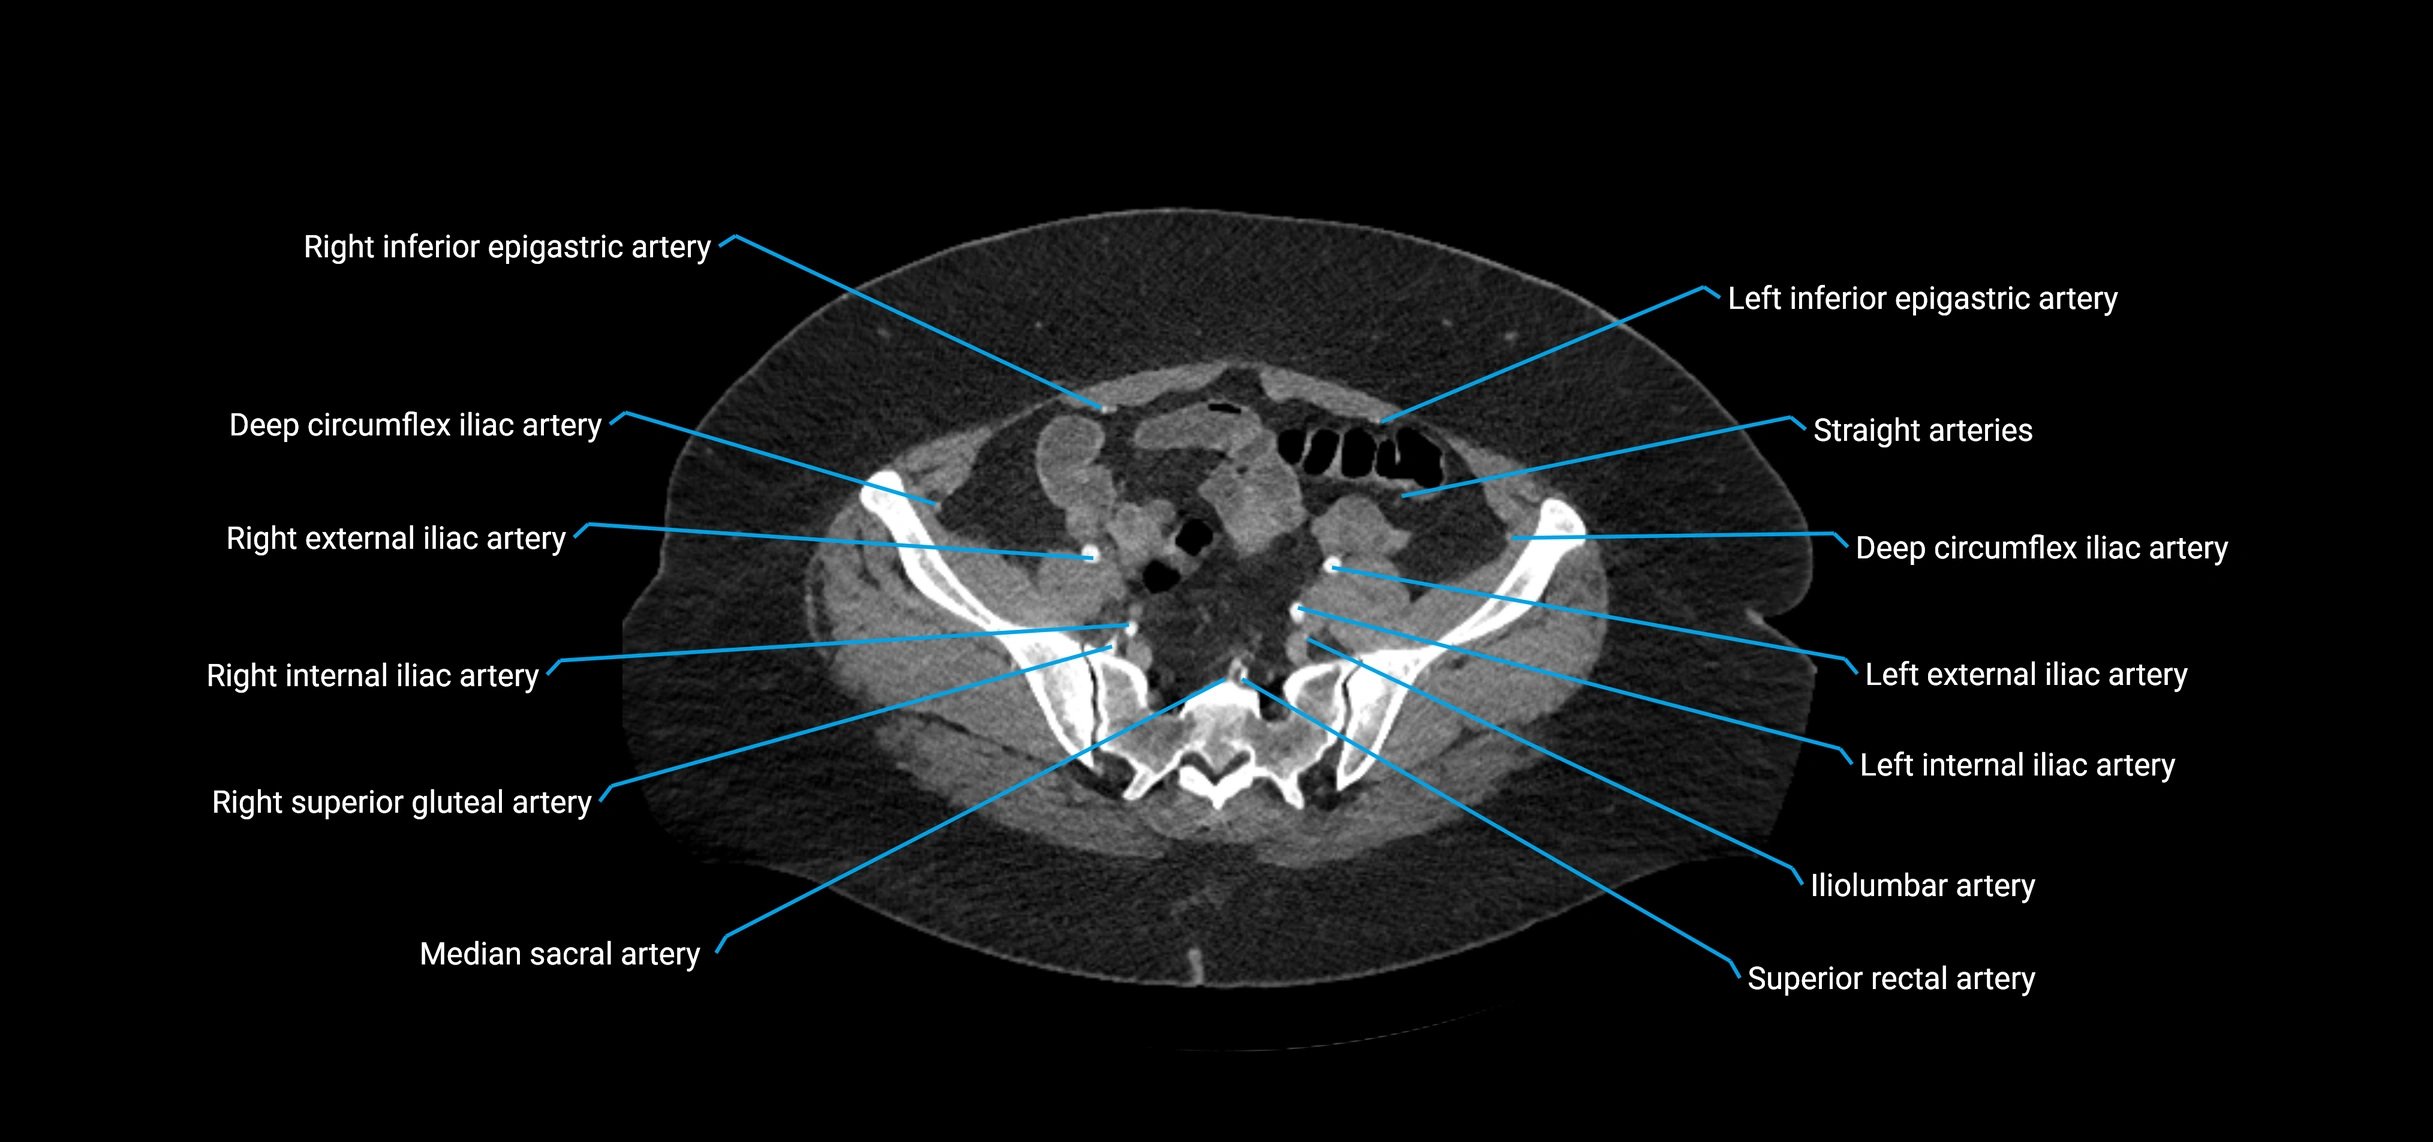

• Parietal branches: inferior phrenic arteries, lumbar arteries, median sacral artery

• Terminal branches: right and left common iliac arteries

Contrast-enhanced CT (CTA):

• Gold standard for abdominal aortic imaging

• Provides excellent detail of lumen, wall, aneurysm, thrombus, and branch vessels

• Multiplanar and 3D reconstructions help in aneurysm measurement, stent graft planning, and dissection evaluation

• Detects acute rupture, traumatic injury, or occlusion with high sensitivity